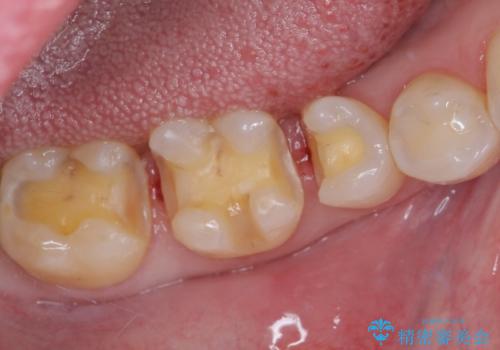

そして次の来院時、セラミックインレーを装着し、噛み合わせなどの調整を行います。

自然な色調で大変満足されました。